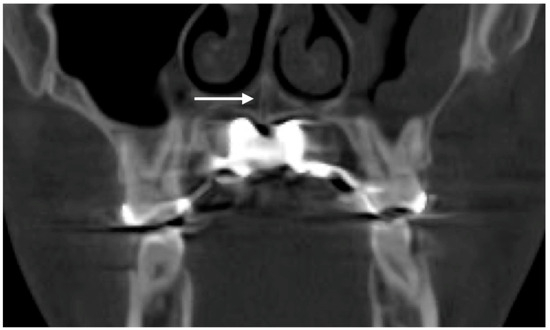

Background/Objectives: Mini-Screw-Assisted Rapid Skeletal Expansion (MARPE) appliances have been widely used for maxillary skeletal expansion in non-growing subjects and adolescents with a fused midpalatal suture. The current case report describes the immediate 3D cephalometric changes in the skeletal and soft tissue parameters, [...] Read more.

Background/Objectives: Mini-Screw-Assisted Rapid Skeletal Expansion (MARPE) appliances have been widely used for maxillary skeletal expansion in non-growing subjects and adolescents with a fused midpalatal suture. The current case report describes the immediate 3D cephalometric changes in the skeletal and soft tissue parameters, along with upper airway volume, shape, and dimensions, in a patient with Skeletal Class I anterior underbite. Methods: The pre- and post-expansion full-face Cone-Beam Computed Tomograms (CBCTs) of a 19-year-old patient who underwent 3D-guided midpalatal piezocorticotomy-assisted MARPE were compared and analyzed using 3D cephalometric software. Both CBCT volumes were re-oriented relative to the Frankfurt horizontal plane (FHP) to accommodate postural changes. Results: The total upper airway volume and minimum upper airway cross-section increased after expansion. The nasal base plane (ANS–PNS) rotated in all three spatial planes, including the sagittal plane (anterior downward and posterior upward rotation, with the center of rotation around the maxillary center of rotation) and the vertical plane (upward rotation on the left side). The maxillary canine and molar cant planes rotated around the center of rotation in the midface, with left upward and right downward rotation. The orientation of the ANS–PNS plane changed due to the leftward rotation of the ANS, with the center of rotation approaching the PNS. Cervical curvature improved from kyphotic to lordotic immediately following expansion. Conclusions: Three-dimensionally guided midpalatal piezocorticotomy-assisted MARPE has been shown to produce midfacial changes in all three spatial planes when evaluated via 3D cephalometric analysis. Comprehensive observational studies are necessary to analyze these changes and their effects for different skeletal classifications. Full article